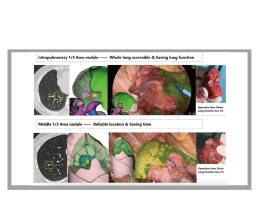

術前或術中完玉成肺結節識別及手術计划規劃,,,,,,貼近剖解學

切除(包括肺內1/3、中段1/3),,,,,,覆蓋特殊位置肺結節

(肋骨阻擋、貼近斜裂胸膜、貼近血管)。。。。。。。。